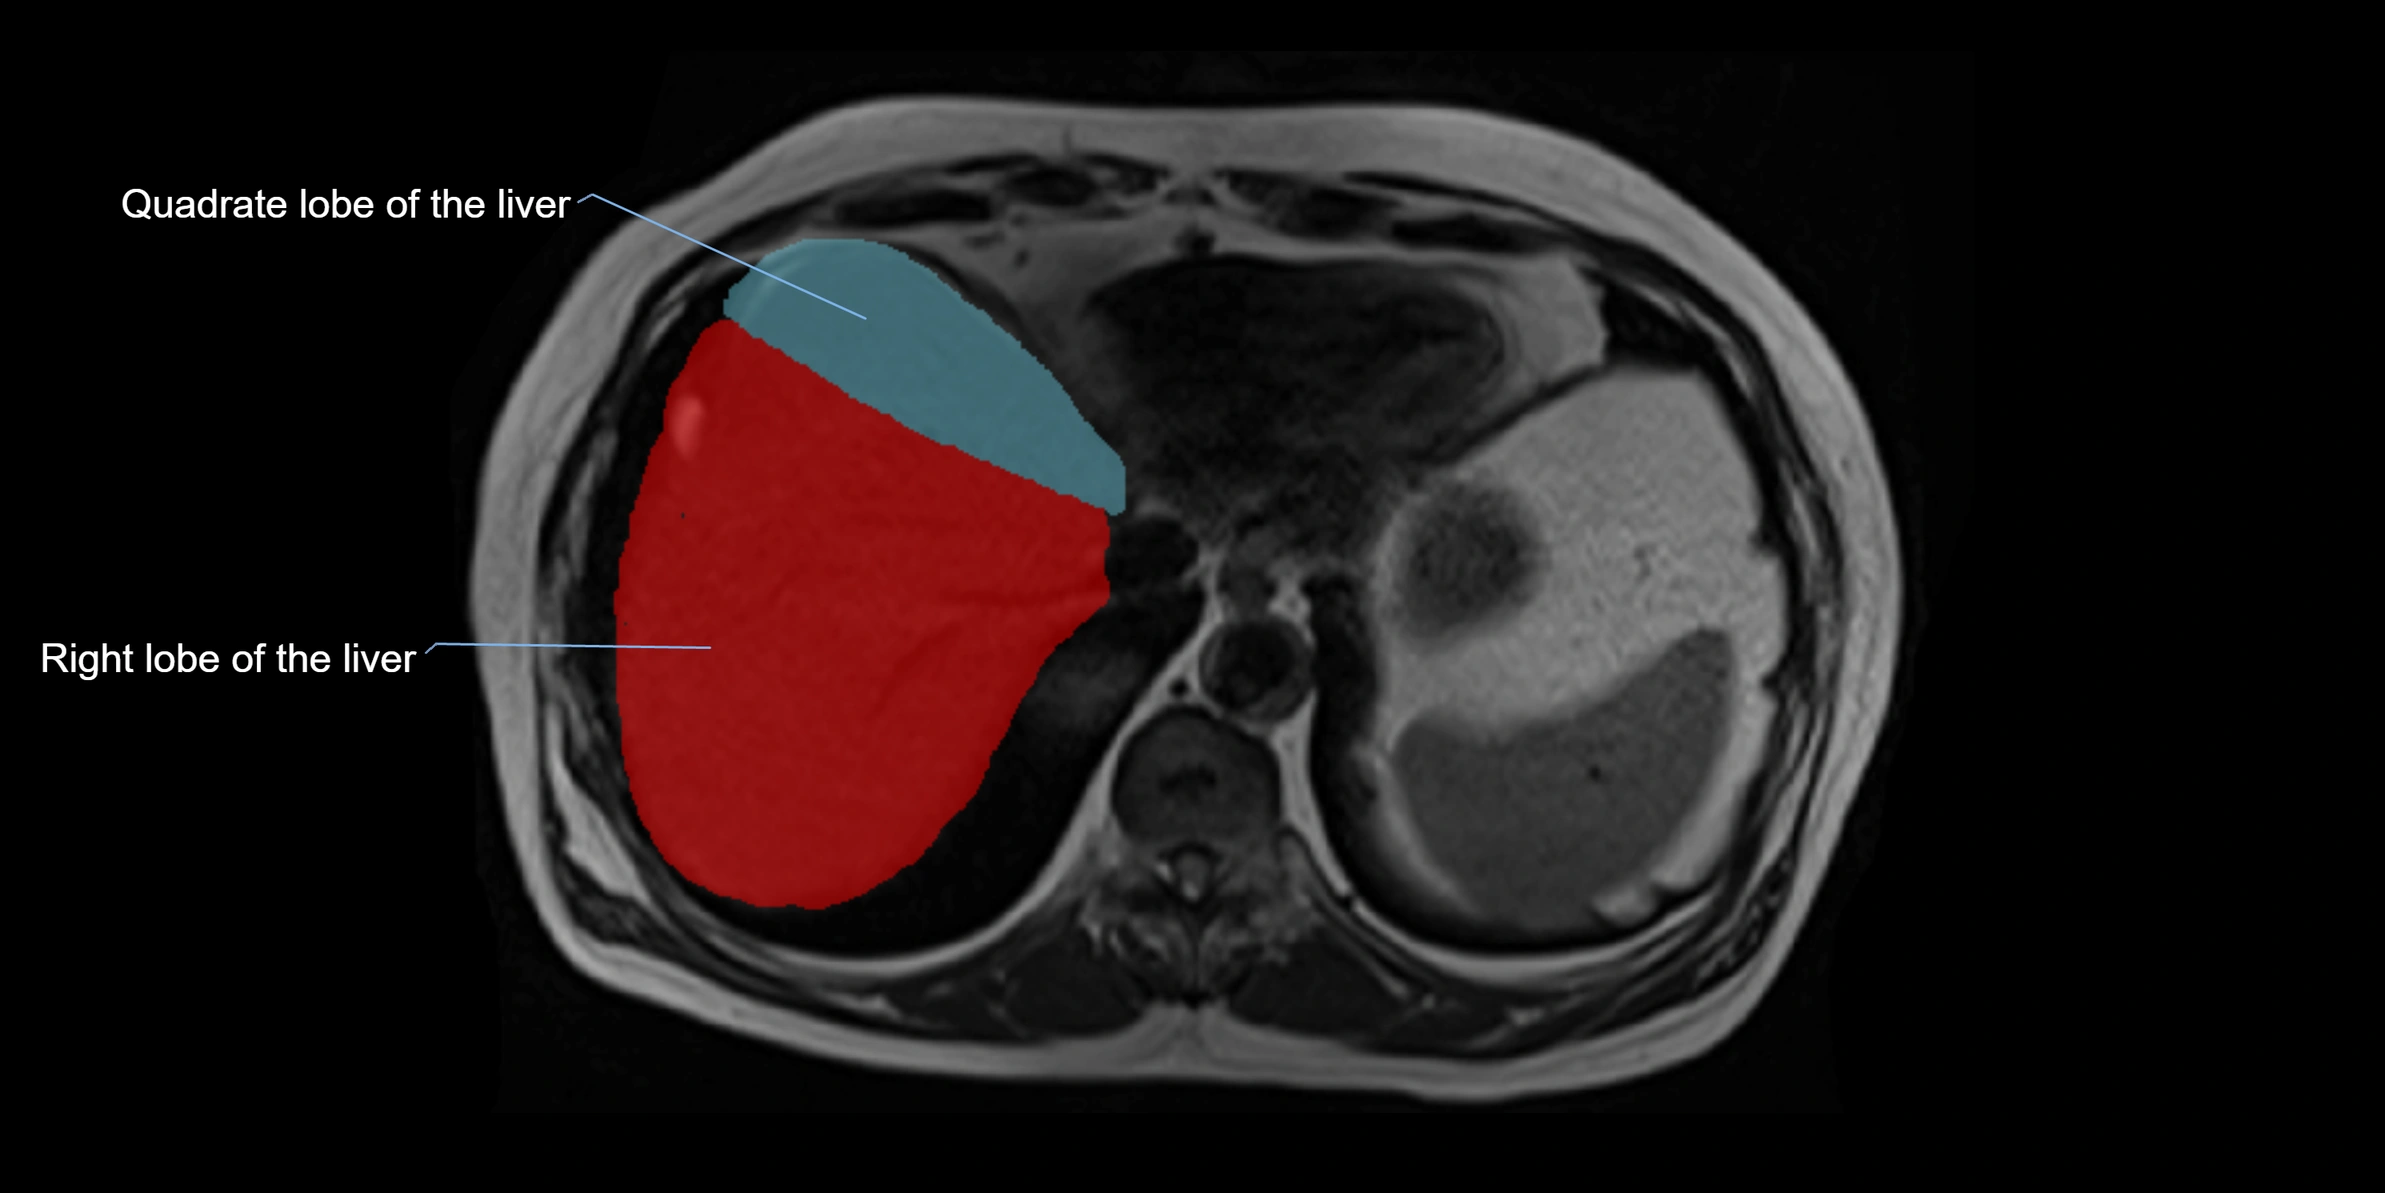

MRI image

image